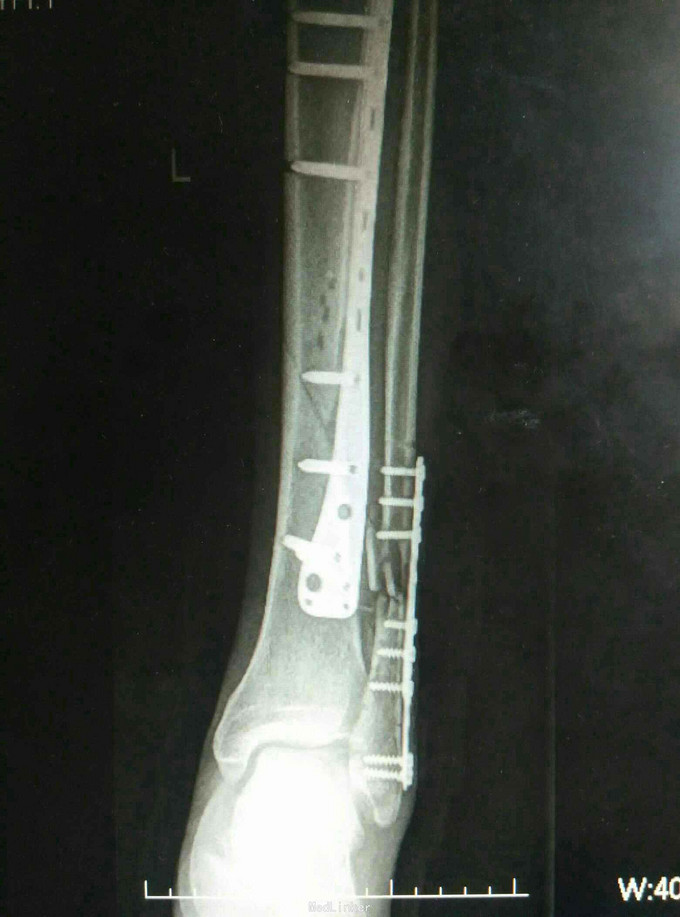

诊断:左胫腓骨远端骨折 治疗:骨折切开复位内固定

讨论:相比上肢尺桡骨双骨折,下肢胫腓骨双骨折更易发生骨筋膜室综合征,应警惕。对胫腓骨碎骨不易过大范围剥离软组织进行复位,以免影响血运得不偿失。